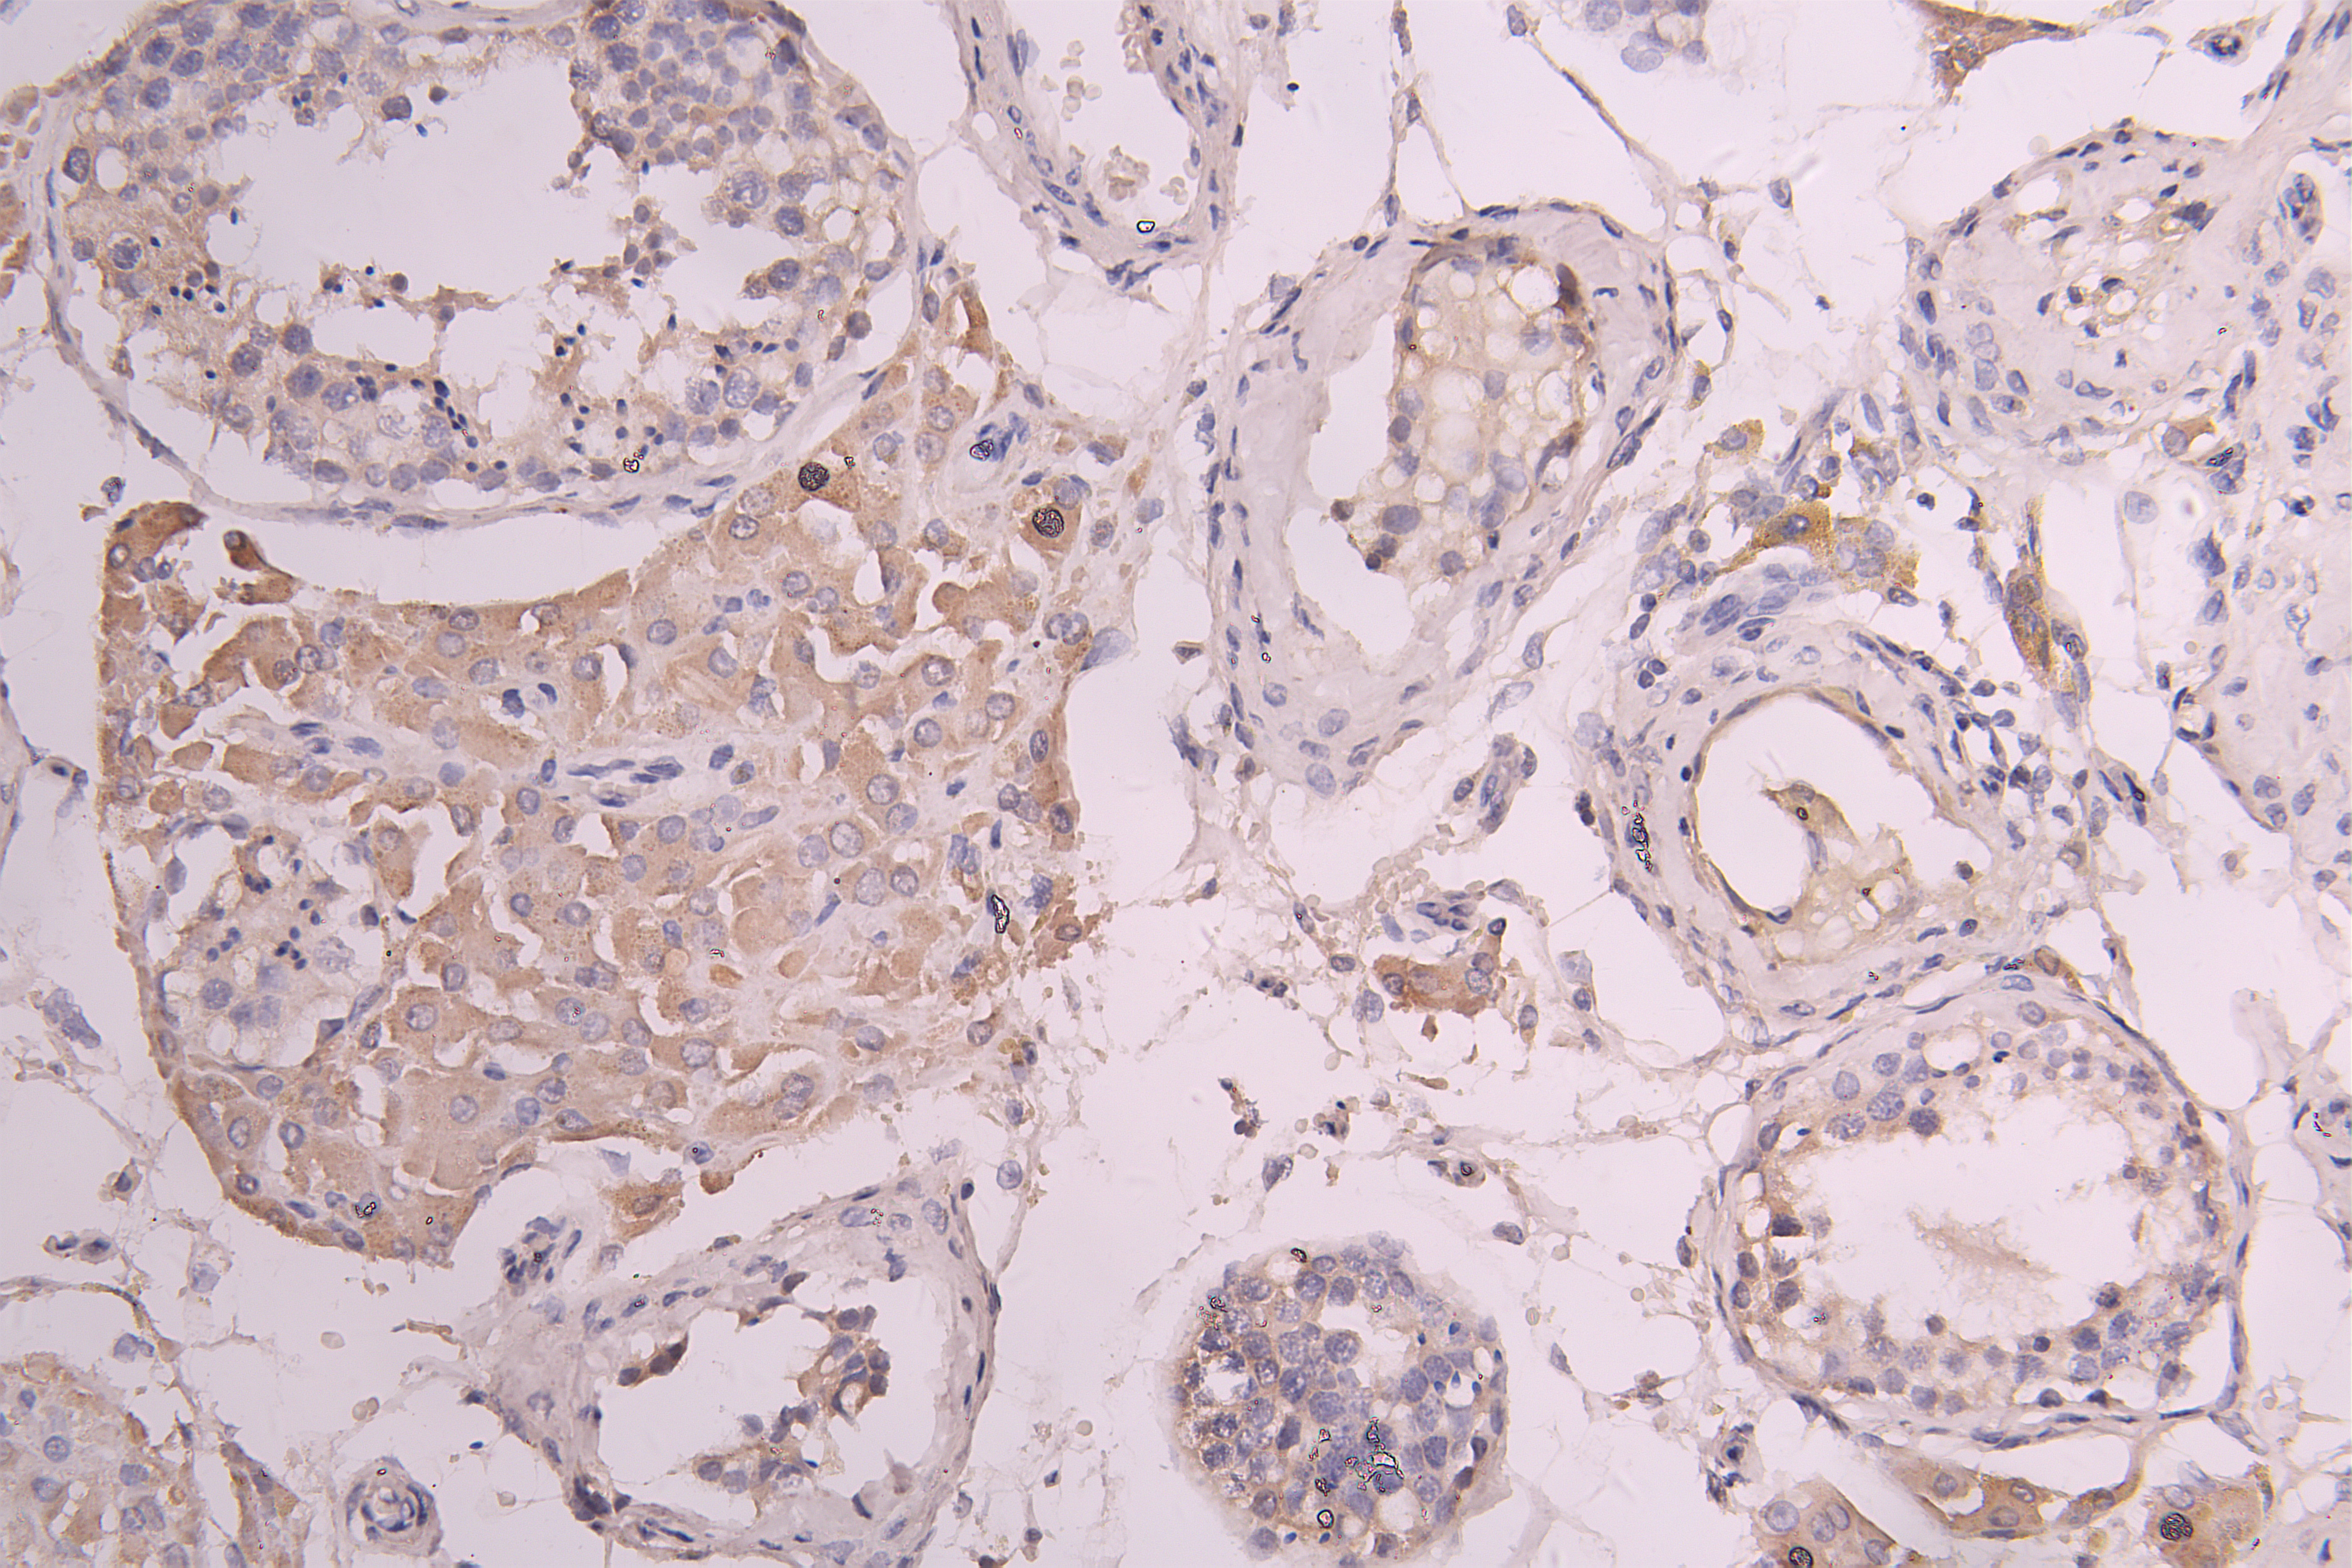

IHC image of CSB-RA860321MA1HU diluted at 1:100 and staining in paraffin-embedded human testis tissue performed on a Leica BondTM system. After dewaxing and hydration, antigen retrieval was mediated by high pressure in a citrate buffer (pH 6.0). Section was blocked with 10% normal goat serum 30min at RT. Then primary antibody (1% BSA) was incubated at 4°C overnight. The primary is detected by a Goat anti-human polymer IgG labeled by HRP and visualized using 0.05% DAB.